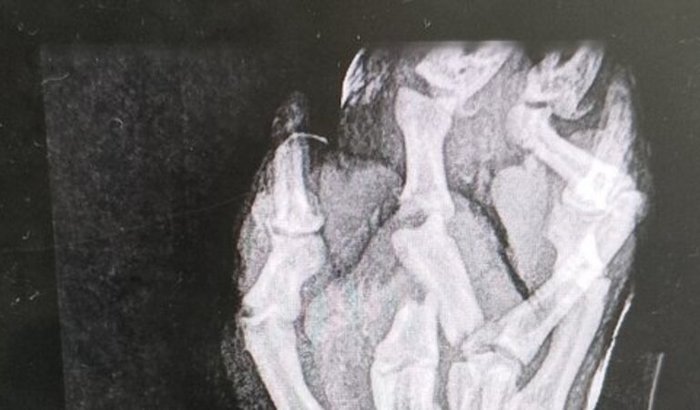

Paçoca foi abandonado e sofreu um acidente na patinha traseira ele precisa ficar internado para o tratamento.  ver tudo

Paçoca foi abandonado e sofreu um acidente na patinha traseira ele precisa ficar internado para o tratamento.